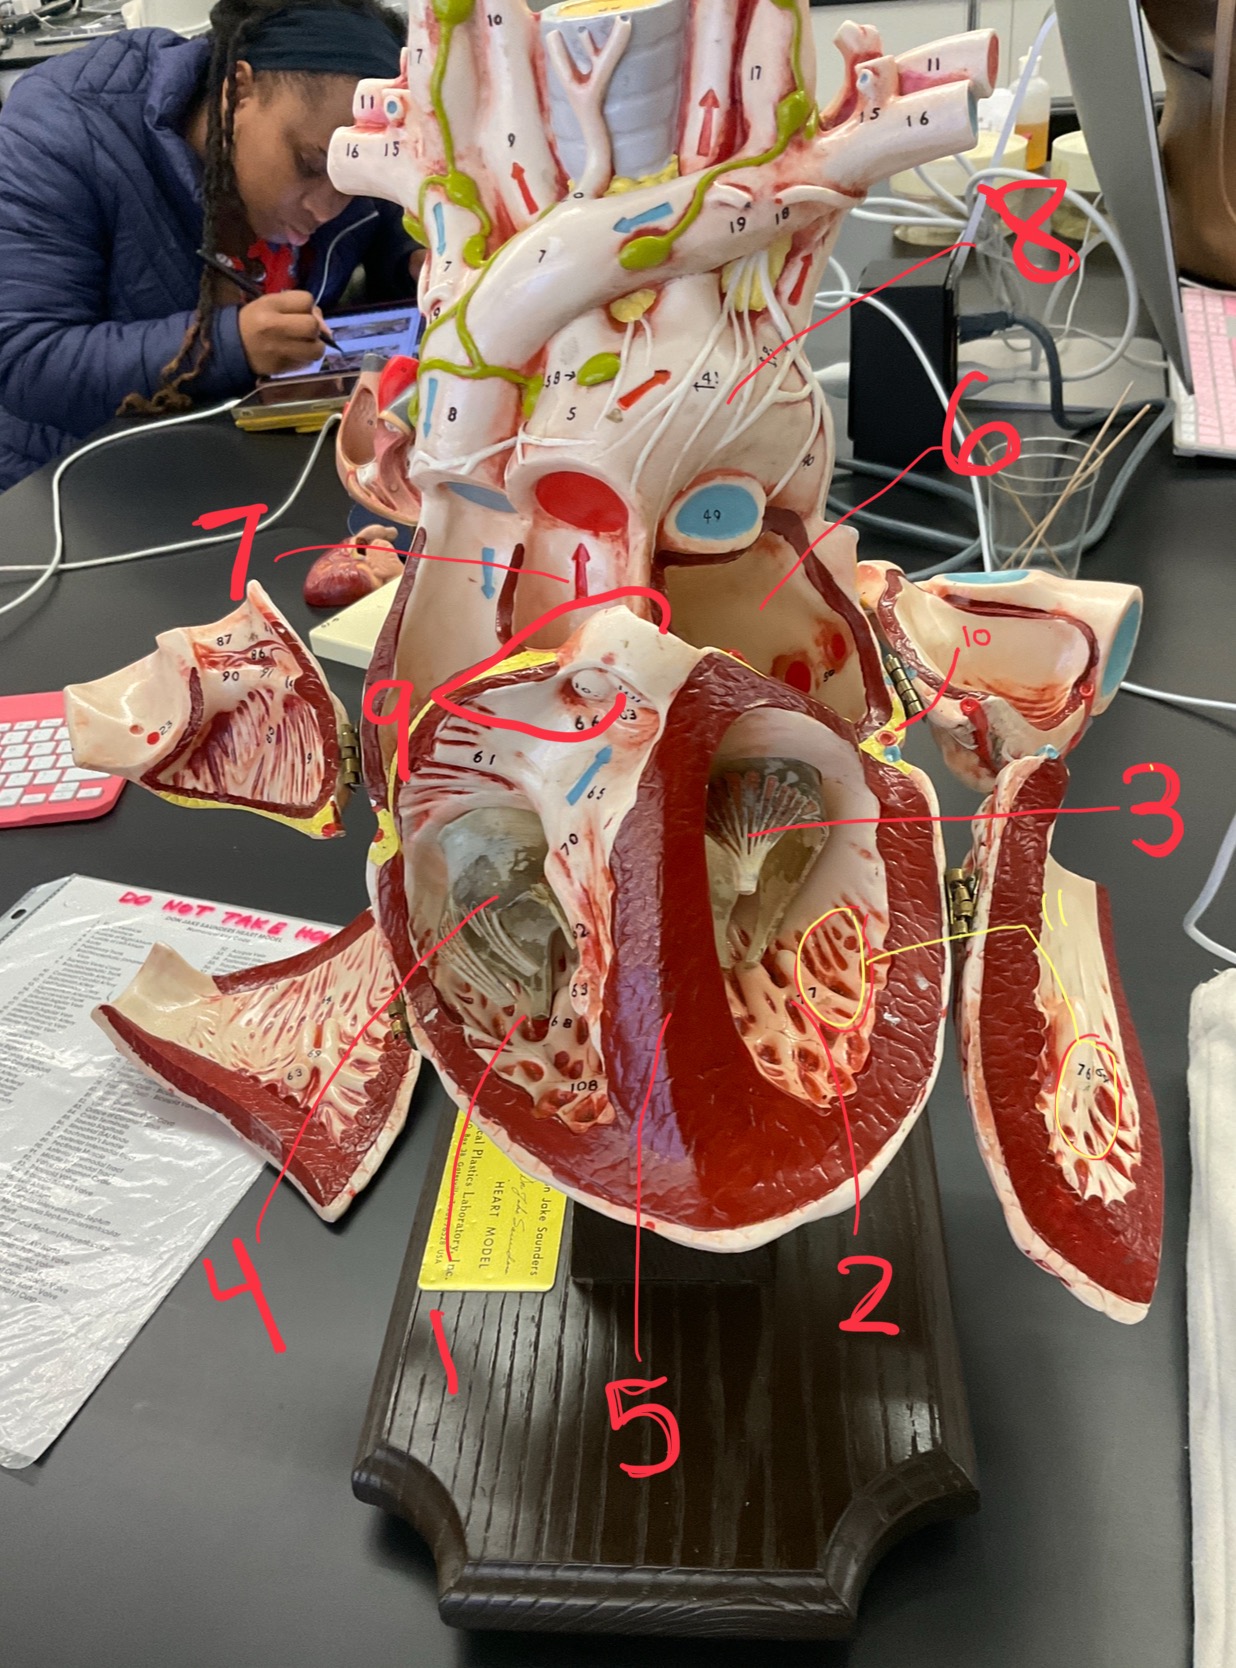

1

epicardium

2

3

endocardium

3

2

myocardium

4

1

coronary sinus

5

2

inferior vena cava

6

3

superior vena cava

7

1

right ventricle

8

2

left ventricle

9

3

bicuspid

10

4

tricuspid

11

5

interventricullar septum

12

6

left atrium

13

7

aorta

14

8

aortic trunk

15

9

pulmonary semi-lunar valve

16

10

atrevoventricullar sulus

17

11 (not smooth part)

trubeculae carneae

18

1

papillary muscle

19

2

chordae tendineae

20

4

pulmonary trunk

21

6

aortic trunk